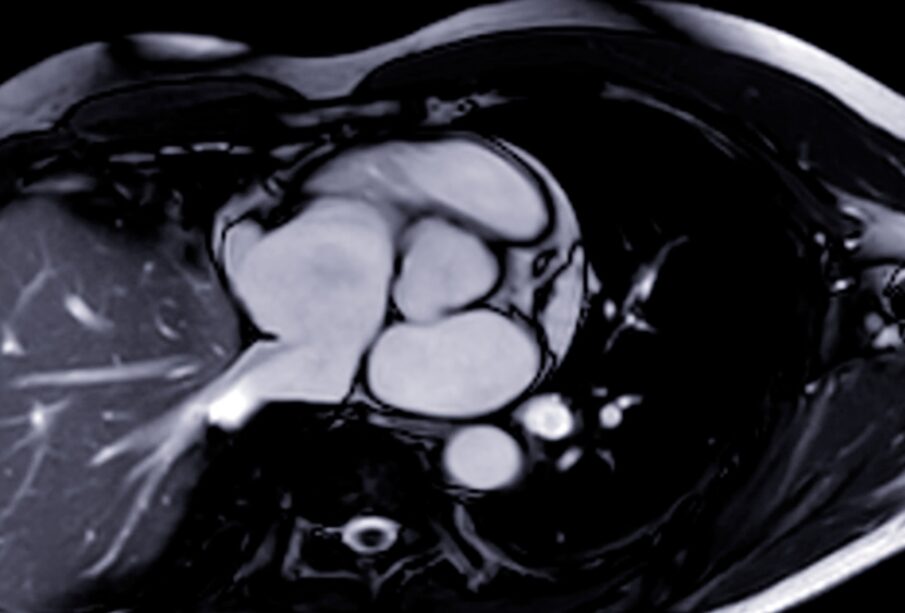

Nauja viso kūno magnetinio rezonanso tomografijos (MRT) paslauga sulaukia vis daugiau dėmesio dėl galimybės aptikti vėžį anksčiau nei pasireiškia simptomai. Viena tokių įmonių, atliekanti šiuos išsamius skenavimus, neseniai paskelbė didžiausio tyrimo rezultatus apie savo tyrimų tikslumą nustatant onkologines ligas.

Vis labiau populiarėjant viso kūno MRT tyrimams, vis daugiau žmonių ieško būdų, kaip iš anksto sužinoti apie galimas sveikatos problemas. Atliekant tokius skenavimus dažnai randama dar nepasireiškusių vėžinių židinių ar kitų pakitimų. Tyrimo metu perduotinoje informacijoje teigiama, kad daugiau nei 2% atrinktų žmonių buvo nustatyta įvairių vėžinių susirgimų. Tai didesnis rodiklis nei kai kurių kitų šiuo metu kuriamų tyrimų, pavyzdžiui, universalaus kraujo tyrimo, kuris siekia 0,5% aptikimo dažnį.

MRT technologija leidžia aptikti įvairius organų ir audinių pakitimus, iš kurių kai kurie vėliau patvirtinami kaip onkologiniai. Be to, beveik du trečdaliai šių atvejų buvo nustatyti tokiose srityse, kurių įprasti profilaktiniai patikros tyrimai įprastai neapima. Tai, pavyzdžiui, inkstų, pūslės ar limfos vėžys.